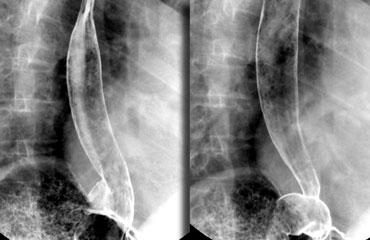

Thăm khám thực quản

Luôn theo dõi quá trình di chuyển của barium qua thực quản cho đến khi vào dạ dày.

Các rối loạn tại vùng nối thực quản-dạ dày thường được bệnh nhân cảm nhận như một vấn đề ở vùng họng.

Lý giải cho điều này là ở những bệnh nhân có tắc nghẽn đoạn xa, trào ngược dạ dày-thực quản hoặc rối loạn vận động, cơ nhẫn hầu phải hoạt động rất mạnh để ngăn thức ăn trào ngược lại vào hầu họng — kèm theo nguy cơ hít sặc.

Trương lực cơ tăng cao này tạo cho bệnh nhân cảm giác có vật gì đó trong cổ họng.

Các hình ảnh là của một bệnh nhân có cảm giác vướng họng (globus sensation).

Nguyên nhân là do trào ngược nặng và tình trạng tăng trương lực cơ nhẫn hầu thứ phát.

Thoát vị cạnh thực quản lớn kèm trào ngược là nguyên nhân gây ra các triệu chứng.

Hình ảnh tối ưu của vùng nối dạ dày-thực quản khi khí trào ngược từ dạ dày vào thực quản đã được phủ thuốc cản quang ở bệnh nhân thoát vị hoành trượt.

Có thể đạt được hình ảnh xuất sắc của vùng nối dạ dày-thực quản bằng cách thực hiện các bước sau:

- Yêu cầu bệnh nhân uống viên sủi zoru-granules (hoặc coca cola) để tạo đầy hơi tối ưu trong dạ dày.

- Dặn bệnh nhân không ợ hơi, mà giữ hơi trong dạ dày cho đến thời điểm nuốt.

- Đặt bệnh nhân ở tư thế chếch trước-trái (left anterior oblique).

- Nâng mặt bàn lên 45 độ.

- Nuốt barium tỷ trọng cao để phủ thực quản tối ưu.

- Chụp hình ảnh khi khí trào ngược từ dạ dày vào thực quản đã được phủ barium.